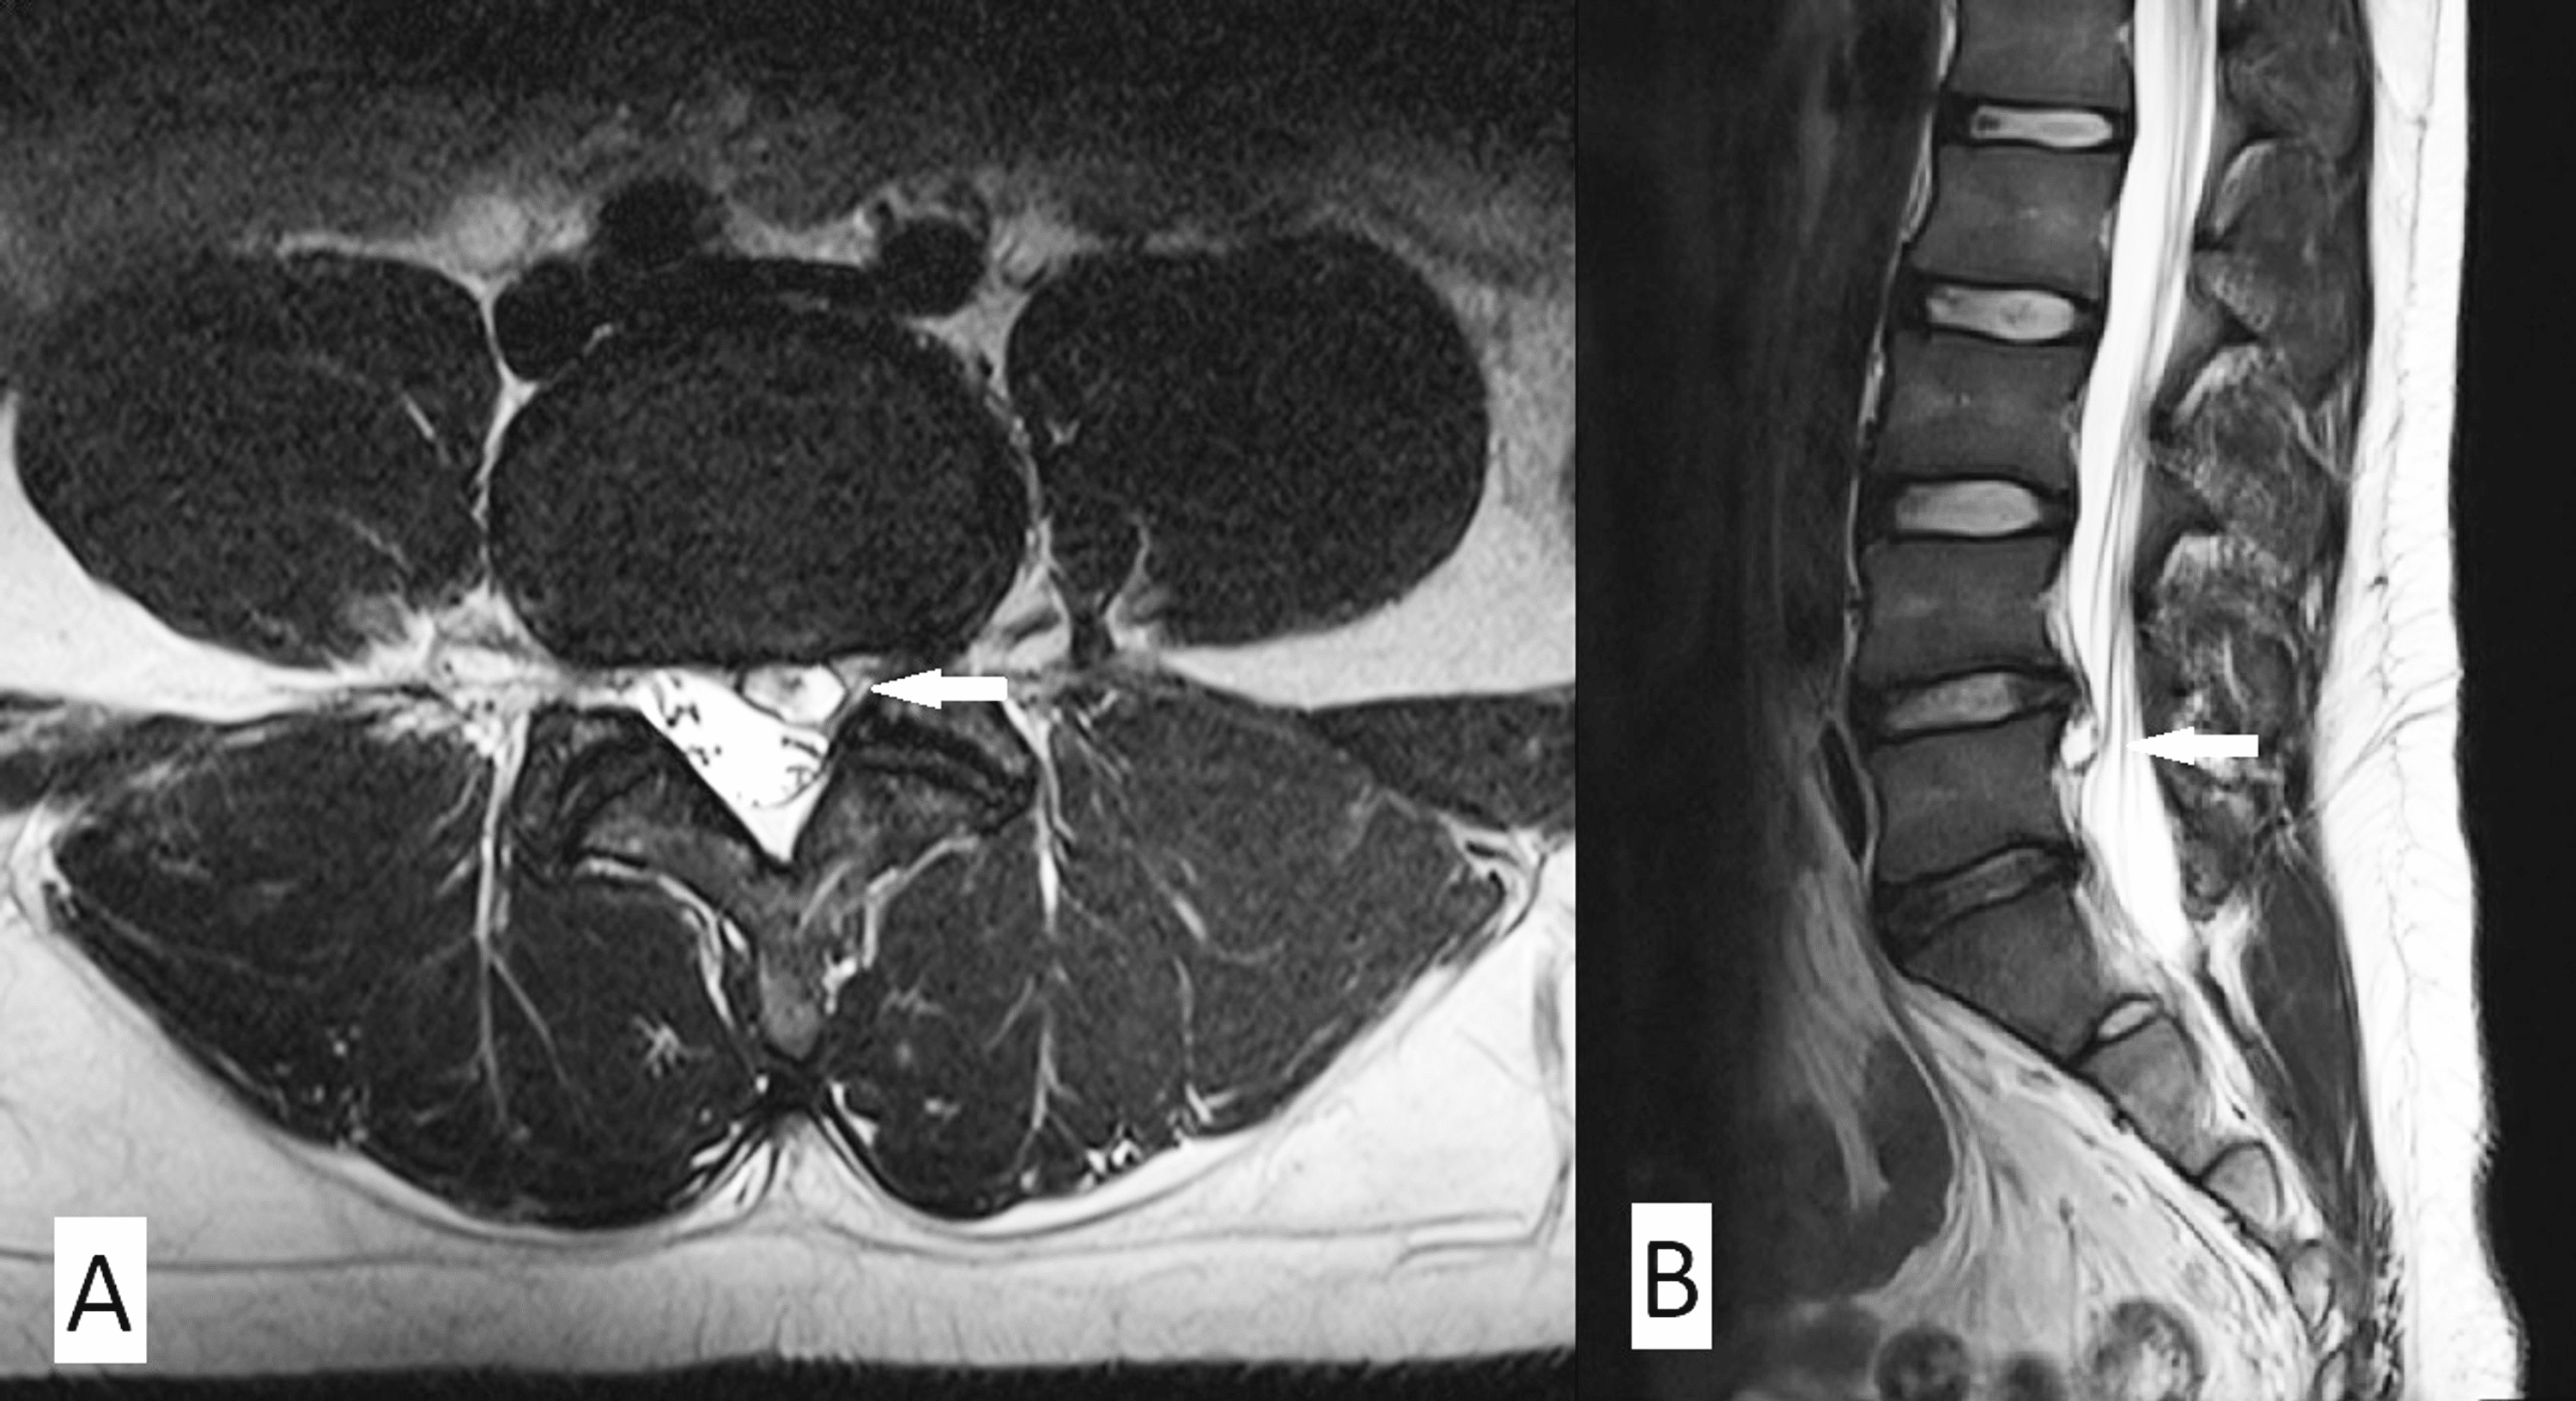

Axial MRI of a discal cyst. (A) Discal cyst showing low signal... Download Scientific Diagram Vertebral Disc Cyst They represent intraspinal extradural cysts in direct contact with the. These usually occur at the base (bottom part) of your spine. Ganglion and synovial cysts are benign lumps caused by a buildup of fluid in a tendon sheath or joint capsule. We report a patient with low back pain and radiating leg pain caused by a lumbar. Also known as. Vertebral Disc Cyst.

MRI imaging of the lumbar spine demonstrating a discal cyst with... Download Scientific Diagram Vertebral Disc Cyst We report a patient with low back pain and radiating leg pain caused by a lumbar. Also known as perineural cysts, tarlov cysts grow at the nerve roots in the spine, where they fill with fluid. They most commonly show up on the top of the wrist, but may also affect the feet or the spine. These usually occur at. Vertebral Disc Cyst.